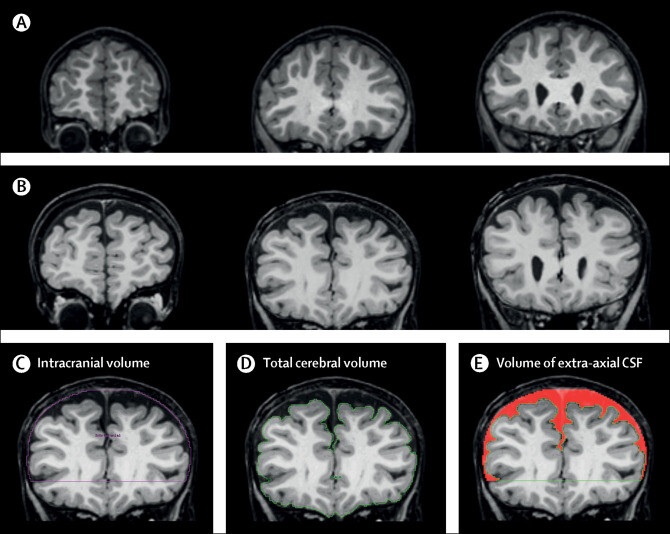

Mit jelent a liquortér tágulat?

CT-n, MRI-n "Mit jelent a liquortér tágulat? Neurológusként magyarázom a külső és belső liquorterek tágulatának okait és jelentését